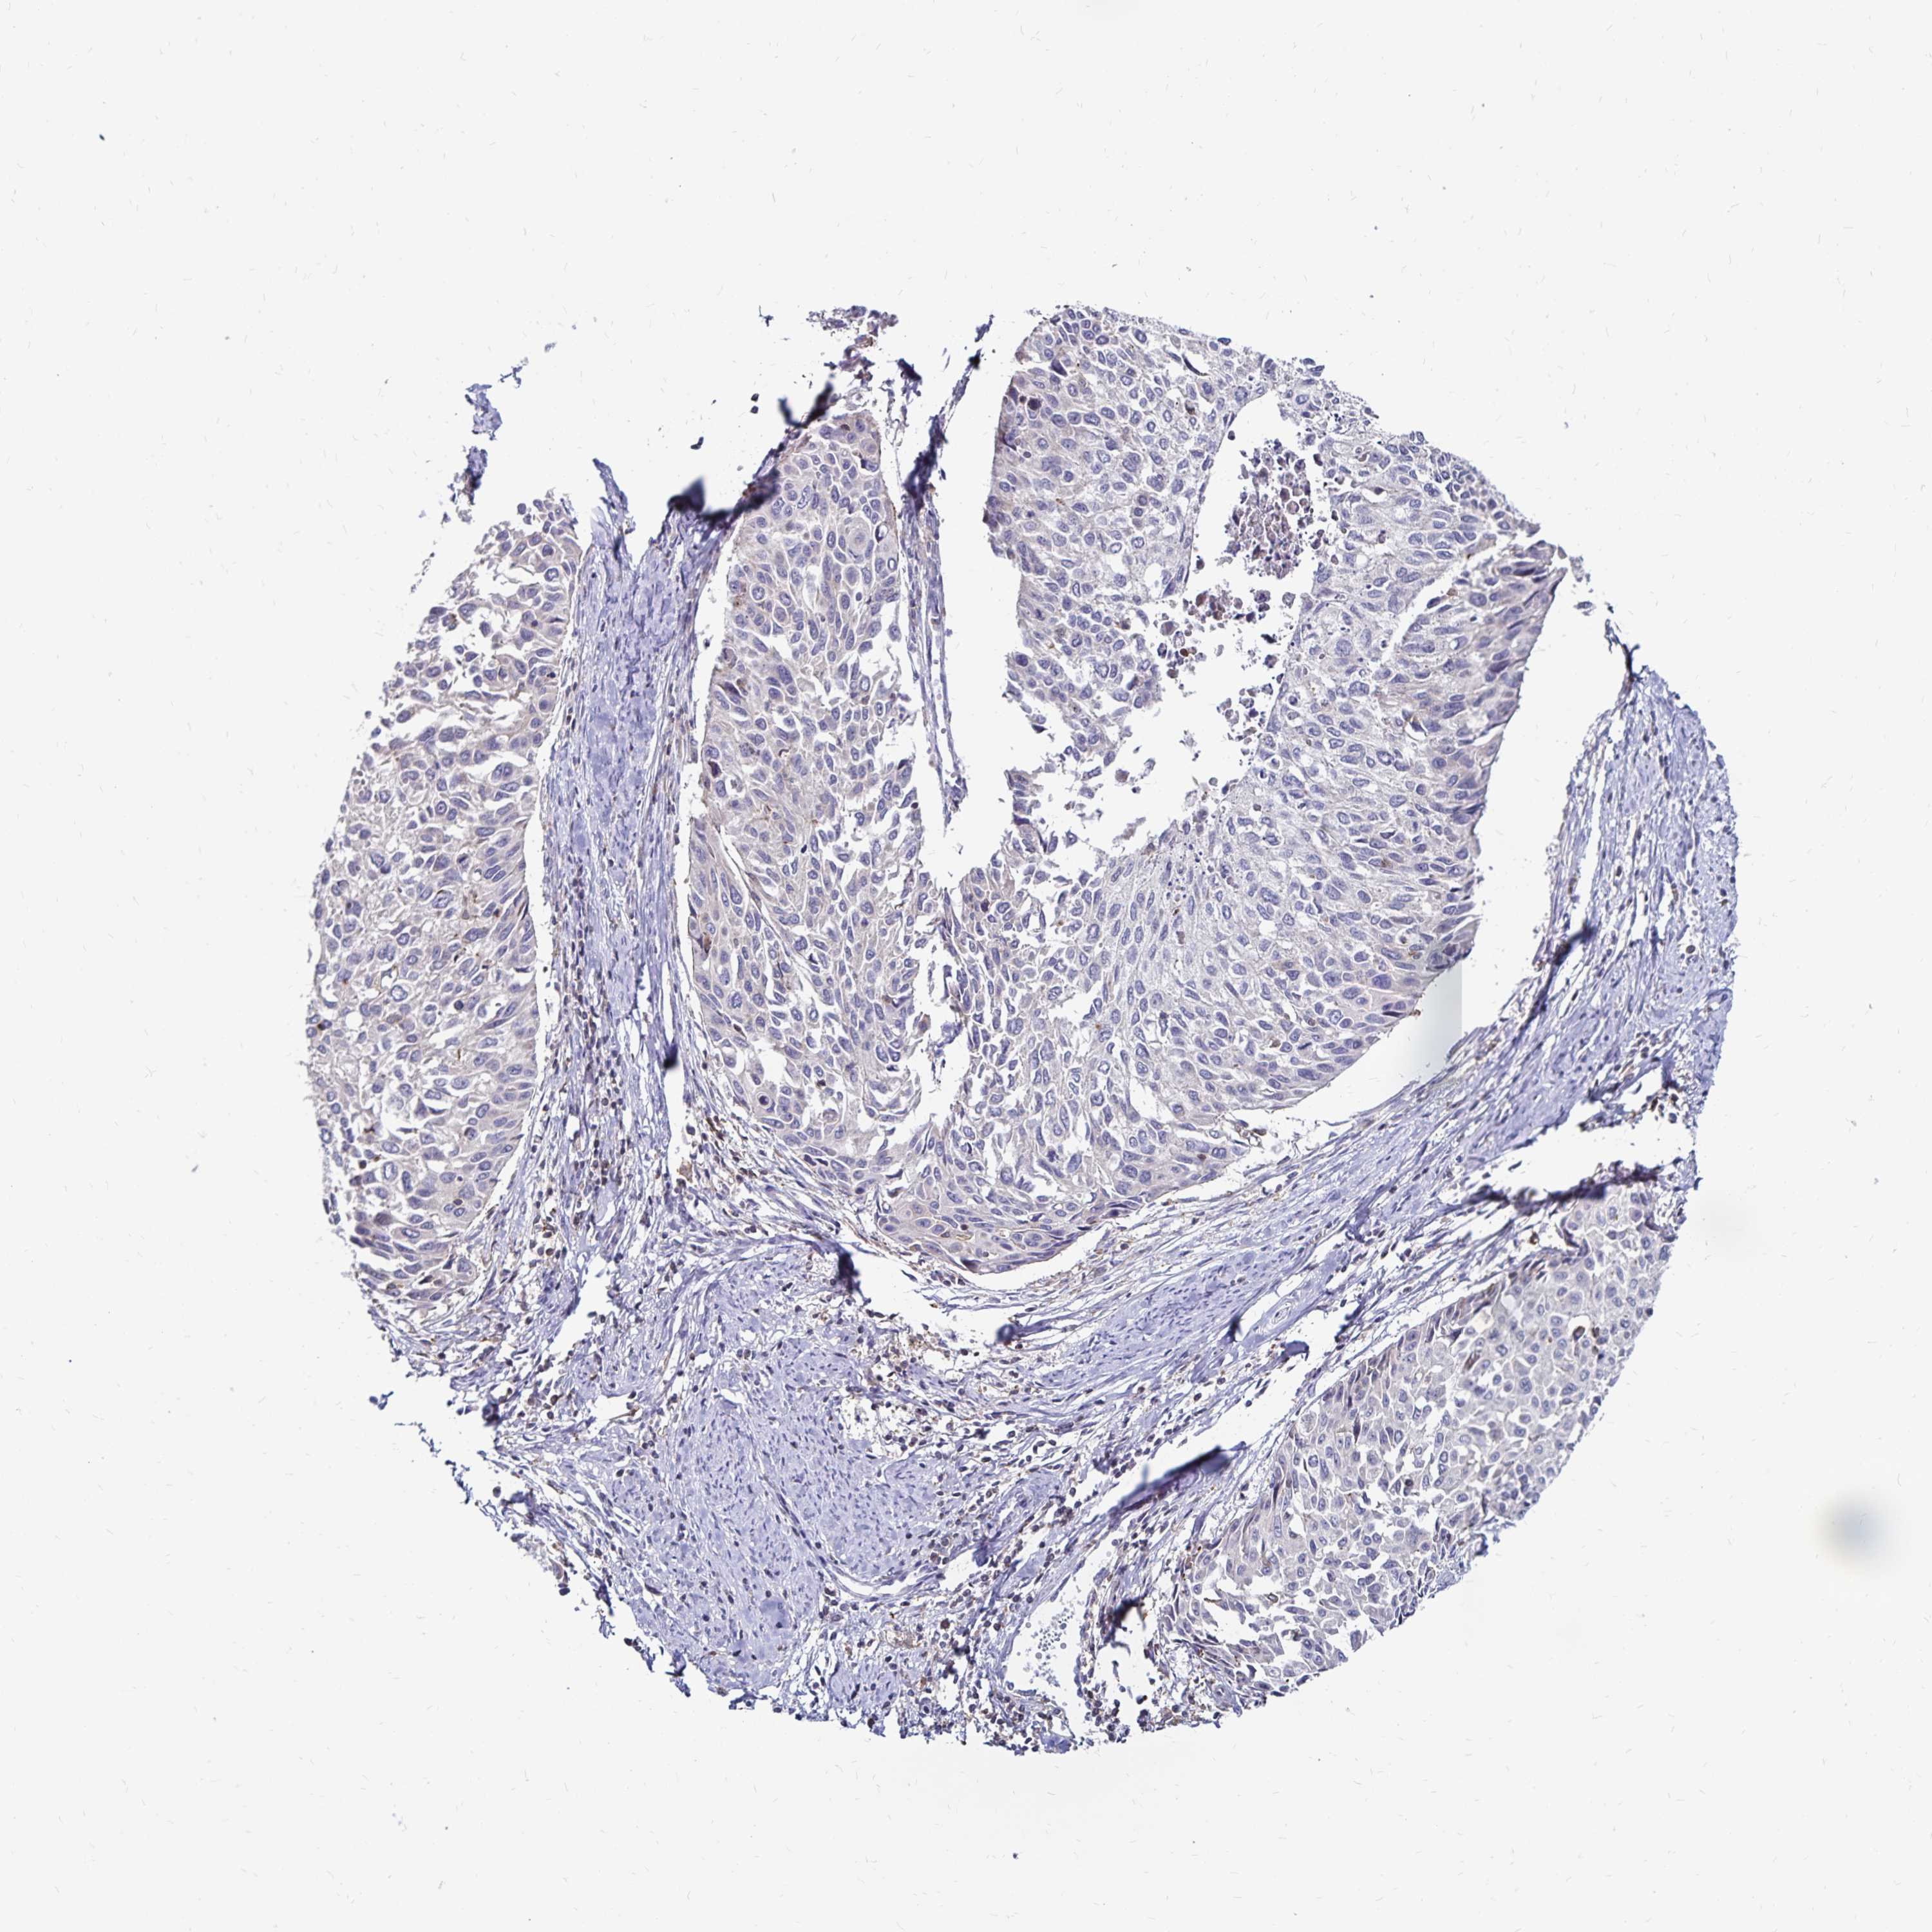

CERVICAL CANCER - Protein expressioni

A mouse-over function shows sample information and annotation data. Click on an image to view it in a full screen mode. Samples can be filtered based on level of antibody staining by selecting one or several of the following categories: high, medium, low and not detected. The assay and annotation is described here.

Note that samples used for immunohistochemistry by the Human Protein Atlas do not correspond to samples in the TCGA dataset.

Antibody stainingi

Antibody staining in the annotated cell types in the current human tissue is reported as not detected, low, medium, or high, based on conventional immunohistochemistry profiling in selected tissues. This score is based on the combination of the staining intensity and fraction of stained cells.

Each image is clickable and will lead to virtual microscopy that enables deeper exploration of all samples and also displays staining intensity scores, fraction scores and subcellular localization as well as patient and tissue information for each sample.

Antibody HPA064055

Staining

High

Medium

Low

Not detected

Intensity

Strong

Moderate

Weak

Negative

Quantity

>75%

75%-25%

<25%

None

Location

Nuclear

Cytoplasmic/membranous

Cytoplasmic/membranous,nuclear

Squamous cell carcinoma, NOS

Adenocarcinoma, NOS